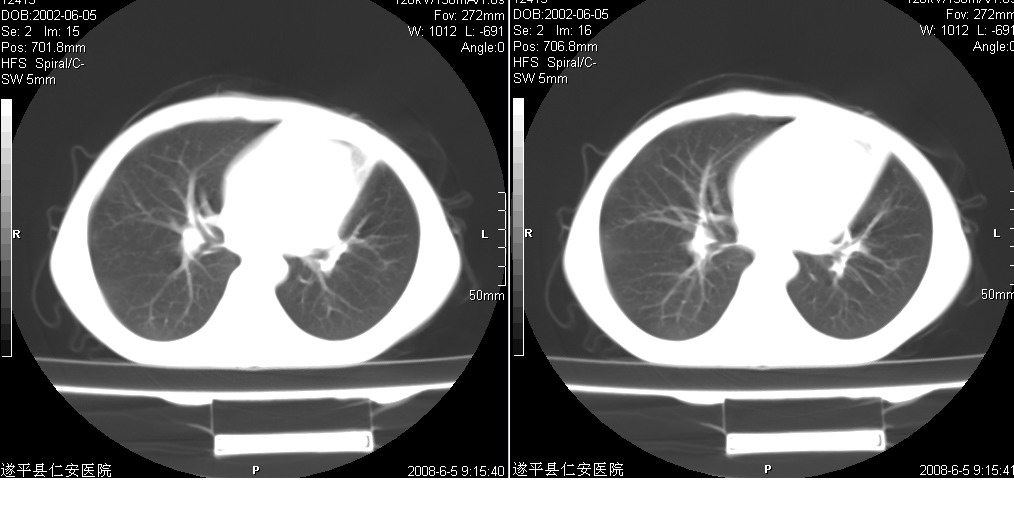

以下是引用xxhwh在2008-6-10 18:40:00的发言:[br]男,6岁,无规则发热一月余,体温在37.8——39度之间。一月前拍胸片示左上肺密度增高影,进行抗炎治疗8天,复查胸片未明显吸收。又改变抗菌素继续治疗半月,照胸片示病灶吸收不明显,行ct检查[br]征象:左上肺前段呈密实影,内可见支气管气像,远侧见絮状模糊影,中上纵隔左移。[br]意见:左上肺前段膨胀不全及感染,考虑为支气管异物或支气管内膜结核所致,[br]建议追问有无异物吸入史,行痰检及ppd检查